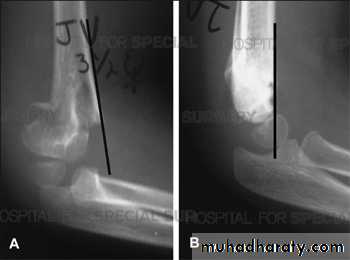

Supracondylar humeral fracture in children is one of the most common fractures seen in the pediatric orthopedic clinic setting worldwide. It's a fracture that occurs at the supracondylar area or the metaphysis of the distal humerus & accounts for 65.4% of upper extremity fractures in children .There are two types of supracondylar fractures in children according to direction of displacement of distal fragment i.e. extension type (97%) and flexion (3%).X-ray of elbow joint (lat. View)

The Gartland classification is a system of categorizing supracondylar humerus fractures (extended type), clinically useful as it predicts the likelihood of associated neurovascular injury, such as anterior interosseous nerve neurapraxia or brachial artery disruption.

The fracture can however be difficult to identify and often a joint effusion is used to increase one's suspicion of the presence of a fracture. Upon examination the doctor will evaluate the arm for signs of damage to the nerves and blood vessels; they will look for swelling and deformity. This will allow the doctor to determine a likely diagnosis. Damage to the elbow is a common injury in children; injuries to blood supply of the arm may necessitate early surgical intervention. The radiographic study of the injured limb should include an anteroposterior (AP) and a lateral view.(AP) –view ( Lat.) –view

anterior humeral line intersects the anterior half of capitellum